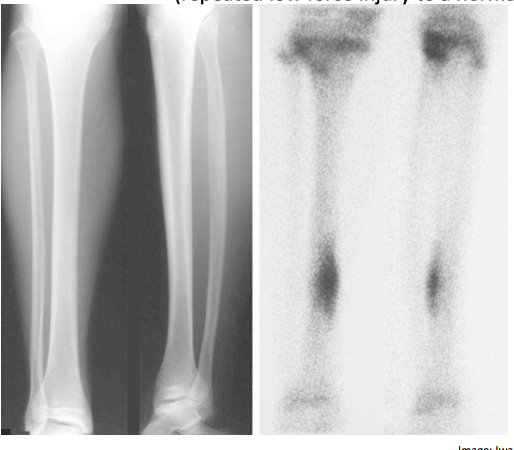

Describe the soft callus stage of fracture healing?

How long does this stage last?

Fibrocartilage formation > holds ends together

Periosteum repairs itself over the outside

Lasts days to weeks